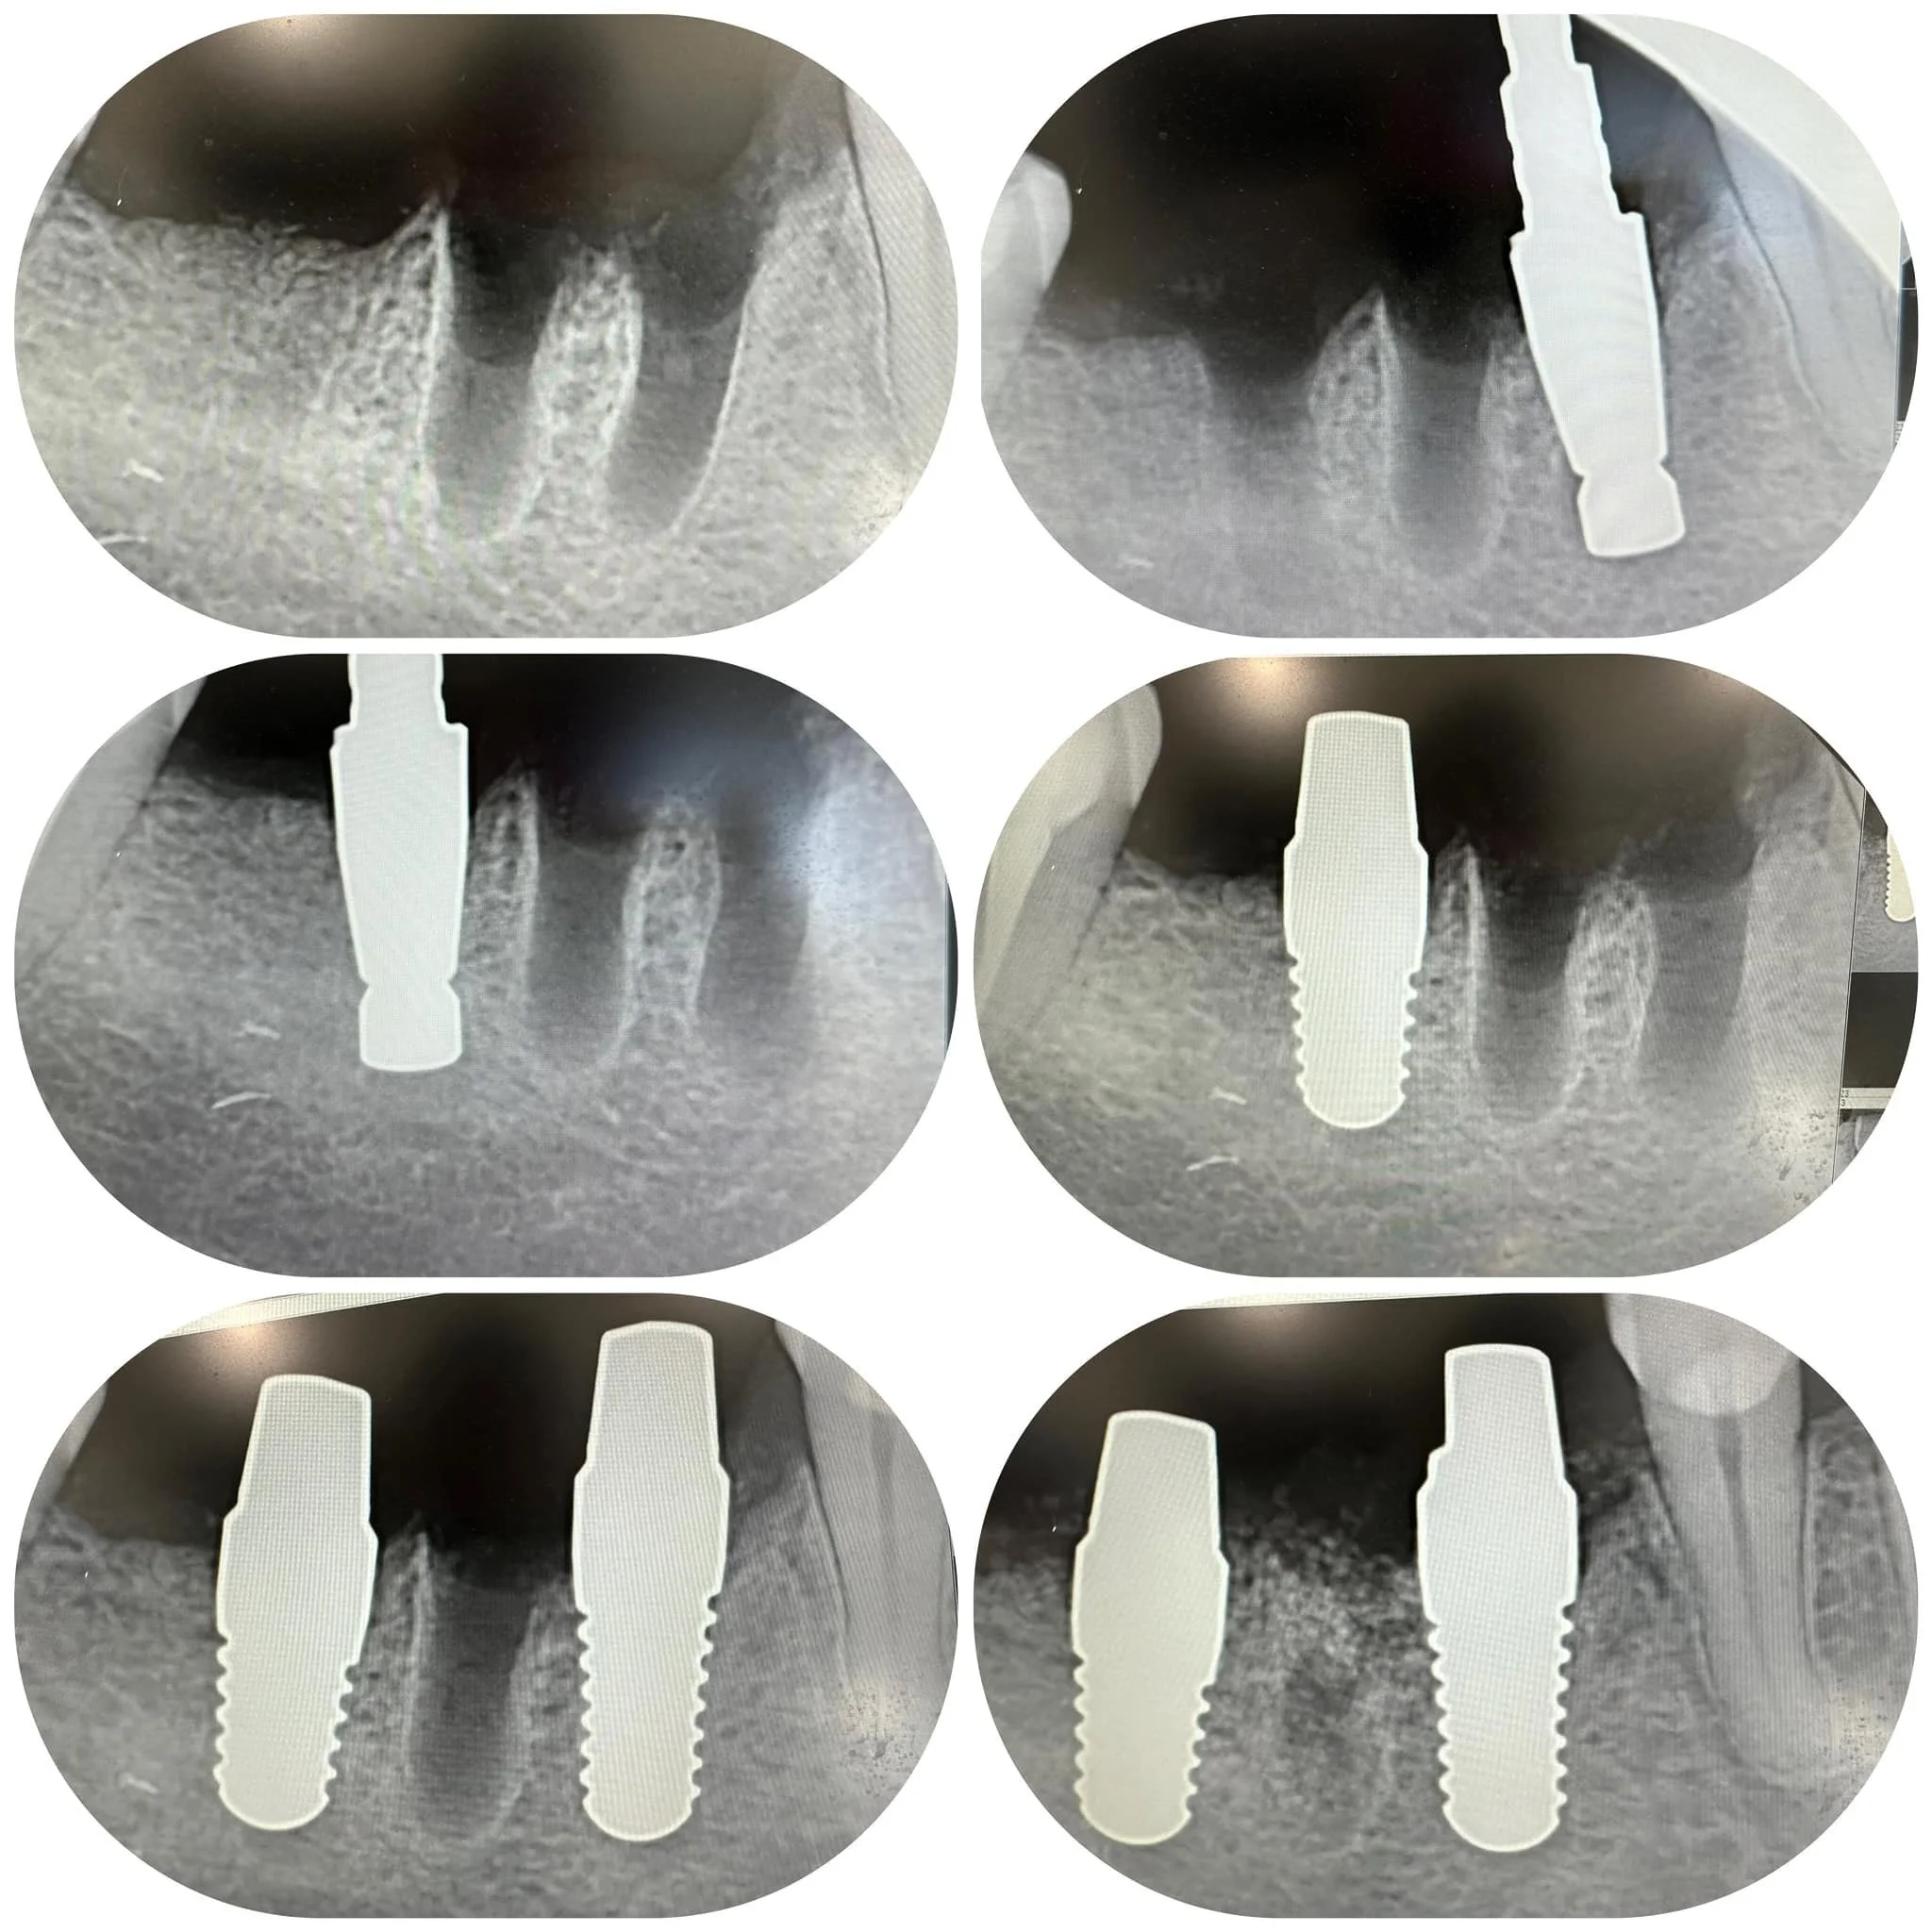

At Family Holistic Dentistry in Boulder Colorado , we place CeraRoot Ceramic Implants. These implants are an excellent option for those seeking a metal-free alternative. This blog explores the attributes of ceramic implants and delves into the reasons behind their increasing use in modern dentistry. CeraRoot implants are a type of dental implant that represents an alternative to traditional titanium implants. They are made from zirconia (zirconium dioxide), a ceramic material known for its durability, strength, and excellent biocompatibility. Here are some key aspects of CeraRoot implants:

One Piece All Ceramic Implants

The One-piece Design Advantage

The CeraRoot implants we use feature a one-piece design, integrating the implant and abutment. This design minimizes the risk of bacterial buildup between components, potentially lowering the risk of peri-implantitis, a condition affecting the tissues around dental implants.